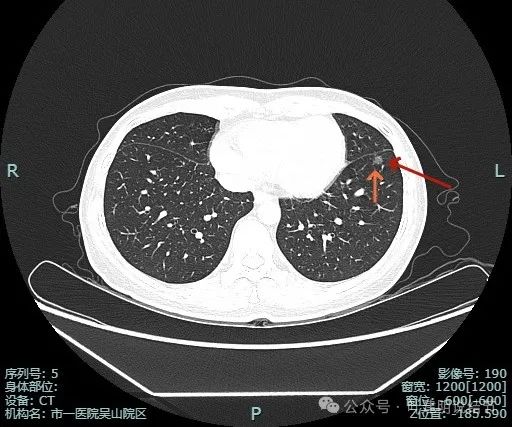

多处血管征,表面毛糙,轮廓清楚,有不太典型的血管弯征,灶内密度稍不均。

叶间胸膜牵拉较平扫上明显,血管进入也明显,整体轮廓清。

灶内有点状偏高密度成分,内部密度稍显杂乱;叶间胸腊牵拉,整体轮廓清。

多支血管进入,而且灶内的血管显得较病灶外略粗与略模糊,叶间胸膜牵拉是有的,力量不强。